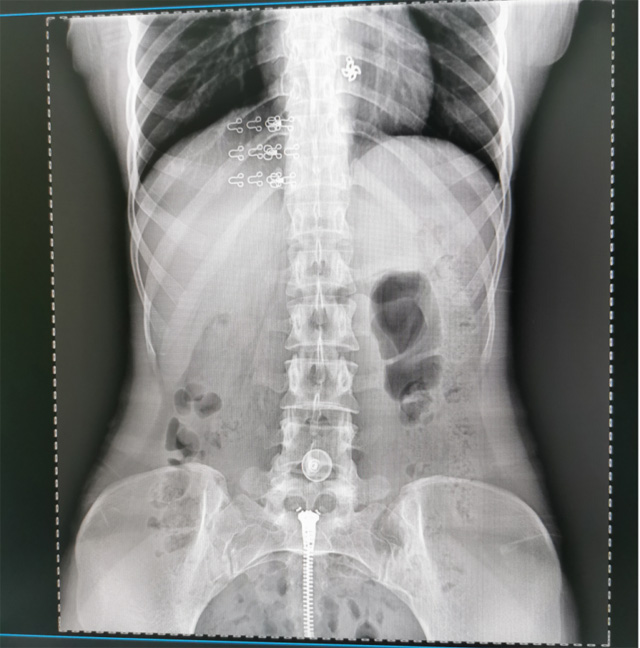

提高醫(yī)院的影像科的醫(yī)療服務(wù)水平,滿足滿足人民群眾不斷增長(zhǎng)的醫(yī)療需求,促進(jìn)醫(yī)療技術(shù)快速發(fā)展。醫(yī)院都引進(jìn)懸吊DR拍片設(shè)備新一代數(shù)字化X線攝影系統(tǒng)。標(biāo)志著醫(yī)院的診療水平又上升一個(gè)新的臺(tái)階。懸吊DR滿足人體頭部、胸部、腹部、腰椎、四肢等部位的數(shù)字?jǐn)z影檢查,可以檢查呼吸系統(tǒng)疾病,心臟系統(tǒng)的疾病、骨關(guān)節(jié)系統(tǒng)的疾病,子宮輸卵管造影、胃腸道造影,.有職業(yè)病體檢篩查塵肺病功能。通過(guò)DR數(shù)字化攝影,分段連續(xù)、重疊采集數(shù)字化圖像,利用軟件對(duì)圖像進(jìn)行拼接的方式來(lái)獲得全脊柱、全上肢或全下肢的圖像。新設(shè)備的圖像更清晰,臨床拍攝避免患者再次搬運(yùn)和移動(dòng)產(chǎn)生的痛苦,是創(chuàng)傷骨折患者的福音。輻射減少受照劑量50%,后處理能力強(qiáng)、圖像質(zhì)量高。有效降低操作難度,縮短工作流程,尤其適合大批量體檢。

具有射線劑量小、圖像清晰度高、誤差小等特點(diǎn),懸吊DR已廣泛應(yīng)用于各級(jí)醫(yī)療機(jī)構(gòu)的體檢中心,越來(lái)越受到臨床醫(yī)生的肯定和患者的青睞。為臨床診斷工作提供更加直觀有效的技術(shù)支持,大大提高了患者就醫(yī)效率從而為患者提供更加優(yōu)質(zhì)的醫(yī)療服務(wù)。提高了其成像質(zhì)量和臨床應(yīng)用價(jià)值,并極大減少了受照輻射劑量。有效滿足了各種常見(jiàn)疾病的臨床診斷和治療需求。以醫(yī)療質(zhì)量為根本,以優(yōu)質(zhì)服務(wù)為導(dǎo)向,竭誠(chéng)為人民群眾的健康保駕護(hù)航。